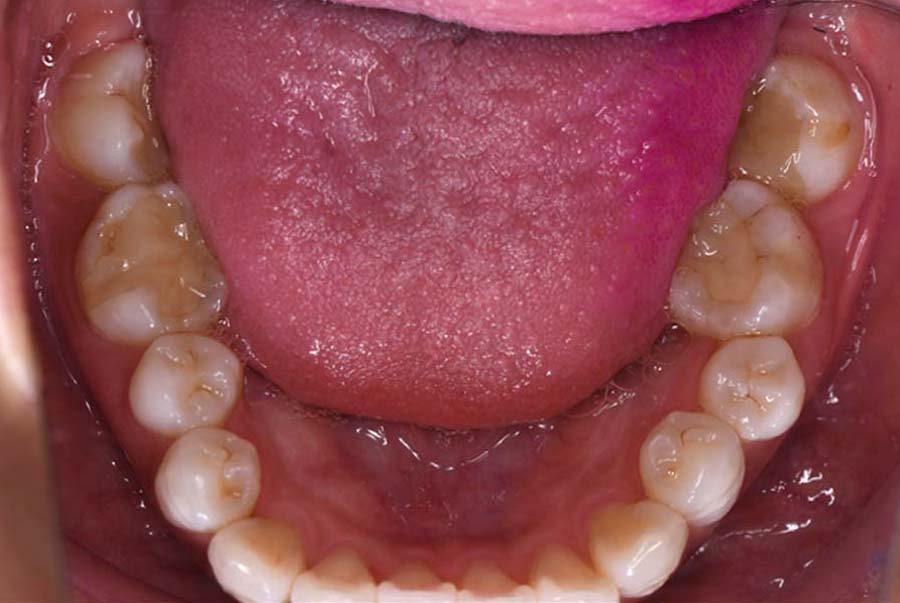

バイトアップ後

![]() |